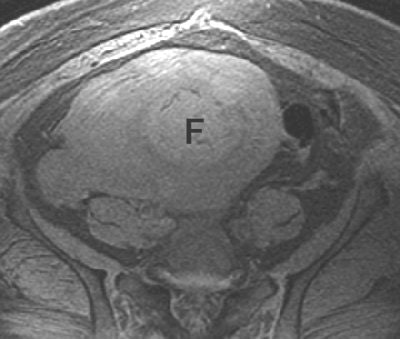

| Forty-seven-year-old woman four days after UAE. Axial, T2-weighted, fat-suppressed, out-of-phase, gradient-echo image obtained through uterus shows high signal intensity of uterine leiomyoma (F) relative to skeletal muscle due to coagulative necrosis and intermediate to high signal intensity of surrounding necrotic uterine myometrium. Torigian DA, Siegelman ES, Terhune KP, Butts SF, Blasco L, Shlansky-Goldberg RD, "MRI of Uterine Necrosis After Uterine Artery Embolization for Treatment of Uterine Leiomyomata" (AJR 2005; 184:555-559). |

In addition, "most of the surrounding uterine myometrium now showed intermediate to high signal intensity on T1-weighted images," the authors wrote. "A diagnosis of near-total uterine necrosis was made, and the patient subsequently underwent a total abdominal hysterectomy.... Necrosis of the endometrium was also present, along with partial or complete occlusion of multiple uterine arterial branches by PVA particles."

They suggested that the MR signs of uterine myometrium necrosis include intermediate to high signal intensity on T1-weighted images, a lack of early and delayed enhancement, and a lack of endometrial enhancement on gadolinium images.